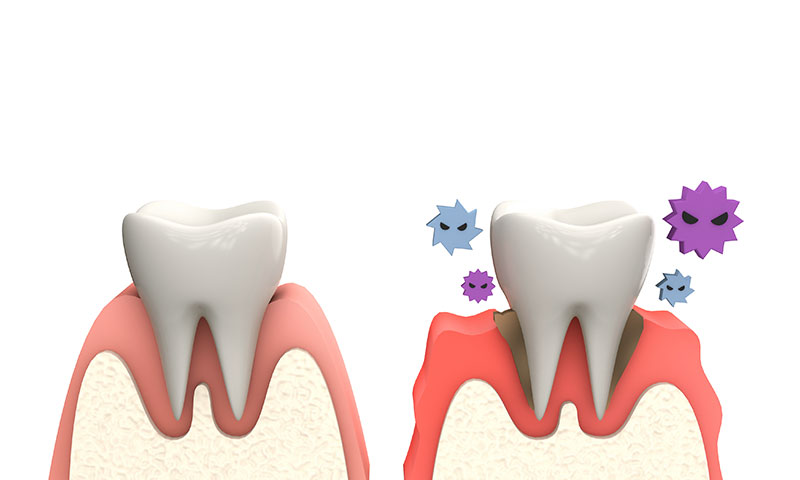

歯周病とはどんな病気か

歯周病とは、歯を支えている顎の骨が溶けてしまう病気です。

多くの人は、歯は歯ぐきに支えられているとお考えではないでしょうか。実際は、歯槽骨と呼ばれる顎の骨に支えられているのです。この歯槽骨が細菌によって溶かされてしまい、歯を支えている土台がなくなり、抜けてしまいます。

歯周病の原因

歯周病の原因は、「歯周病菌」です。

歯周病菌は、歯に付着したプラーク(歯垢)をもとに繁殖します。

健康な状態

健康な歯ぐきは、ピンク色で引き締まっています。スティップリングと呼ばれるみかんの皮のような小さなくぼみが見られます。

歯肉炎

歯のつけ根の表面に、プラークがたまり、歯の周囲や歯と歯の間に炎症が起こります。ブラッシングした時や、固いものを食べると、出血することがありますが、痛みは感じません。